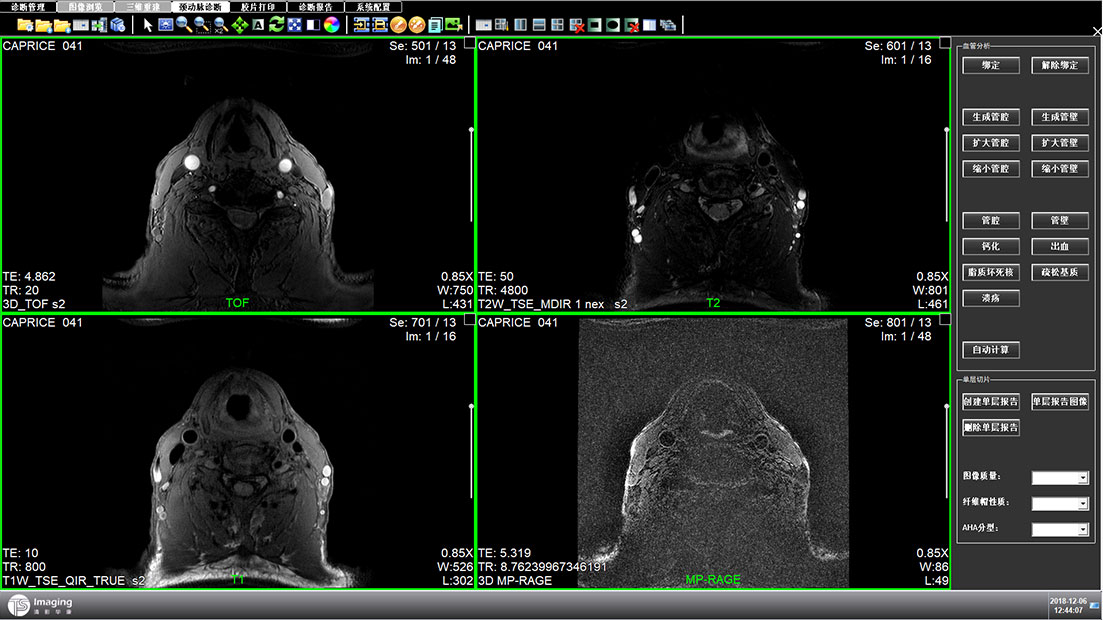

頸動脈診斷頁面

頸動脈診斷頁面整體布局和三維重建比較相似,最大的區(qū)別是右側(cè)的操作區(qū)域,血管分析都為按鍵操作,通過間隔的大小分成三部分。單層切片除了按鍵還有下拉菜單的操作。